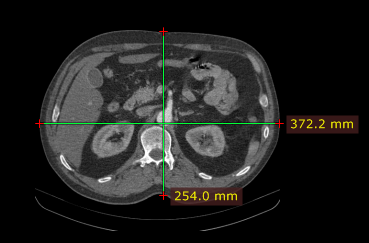

测量结果以毫米或像素显示(当图像文件中不包含校准数据时以像素显示)。

根据校准数据的来源不同,测量标注标签会以不同颜色显示:

已校准(图像中包含像素间距元素)。